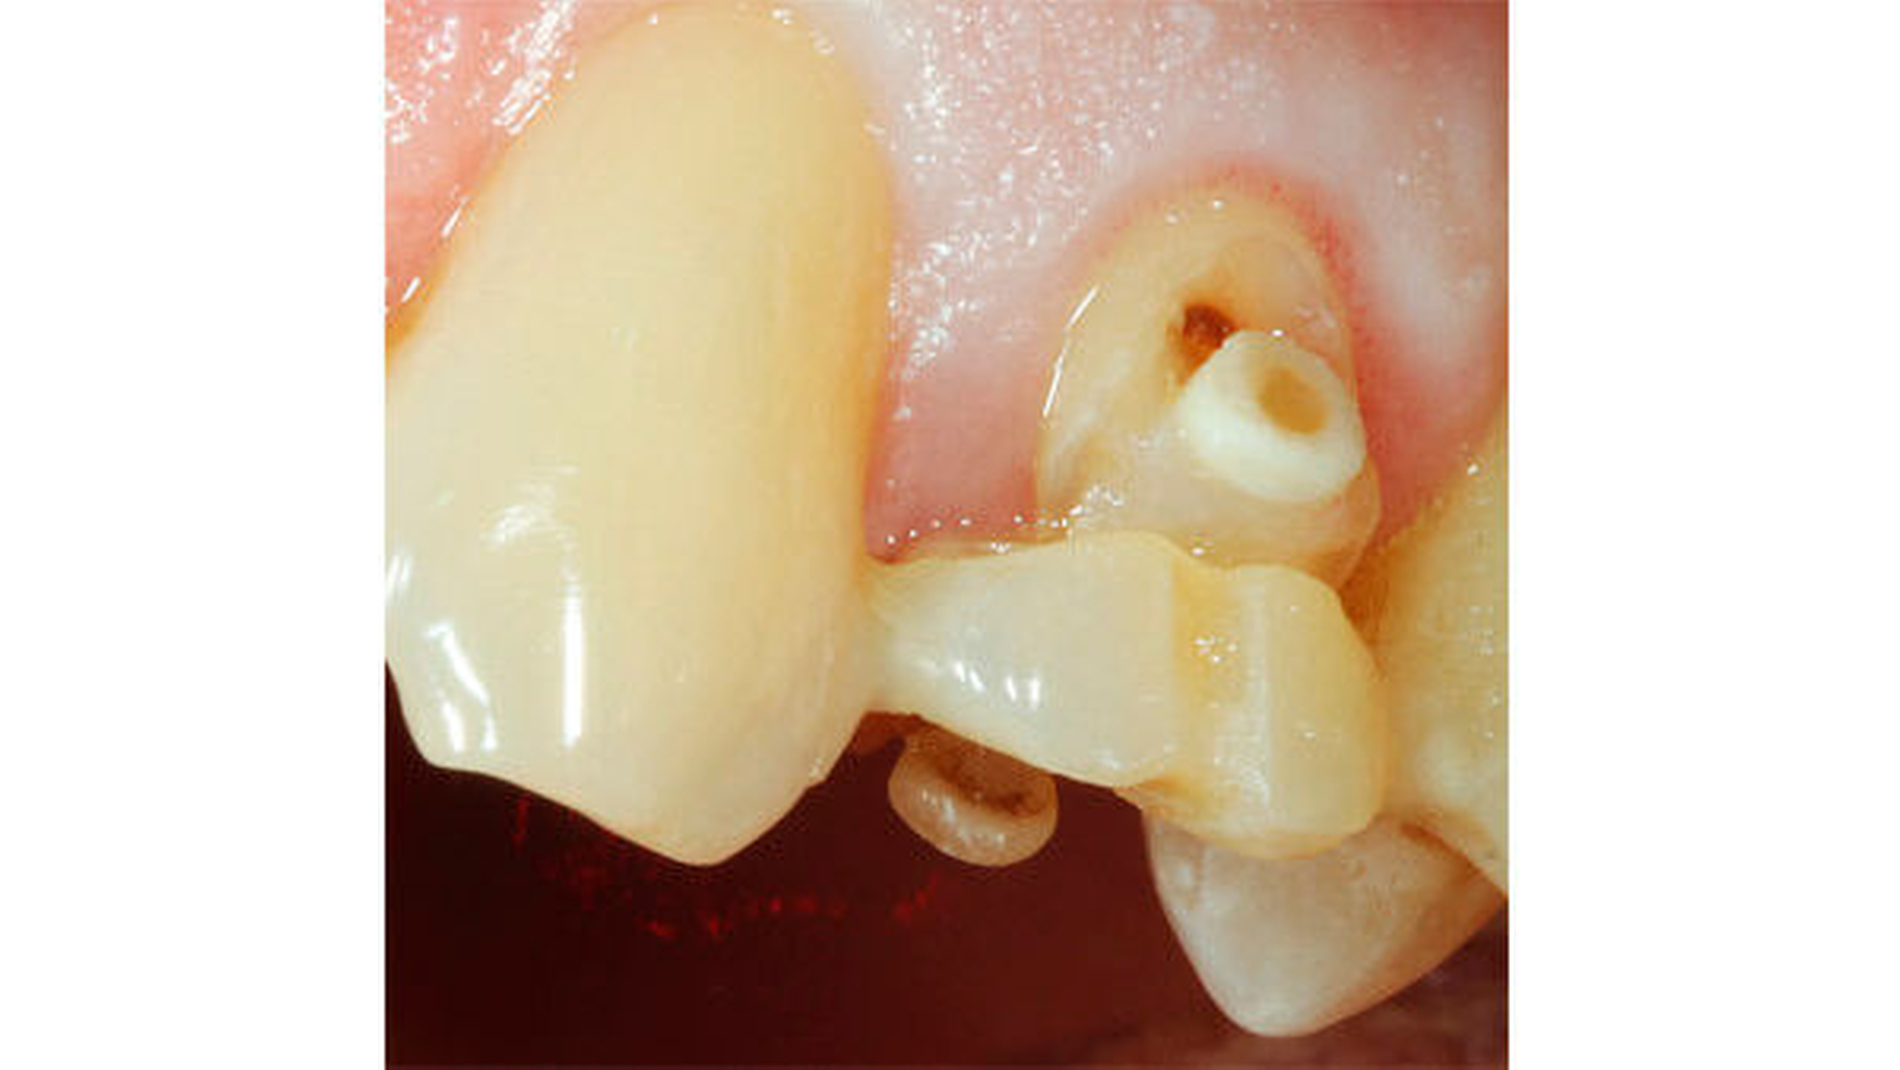

10 | Klinische (Abb. 4) und radiologische Kontrolle nach forcierter Extrusion |

11 | Noninvasive Zahnentfernung mit möglichst viel erhaltener Wurzelhaut (Abb. 5) |

12 | Präparation der Wurzelscheibe/n mit Reinigung und Füllung der Wurzelkanäle (Abb. 6) |